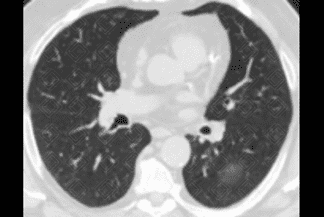

Descrição da figura 8: Tomografia computadorizada do tórax, plano coronal, de outro paciente evidenciando opacidades em vidro fosco periféricas (setas vermelhas), com acometimento pulmonar estimado inferior a 25% do parênquima pulmonar.

Interessante acrescentar que a tomografia computadorizada do tórax tem se mostrado um bom método para estimar extensão de doença . Grosseiramente, estimamos em acometimento inferior a 25% , entre 25-50% e superior a 50% .